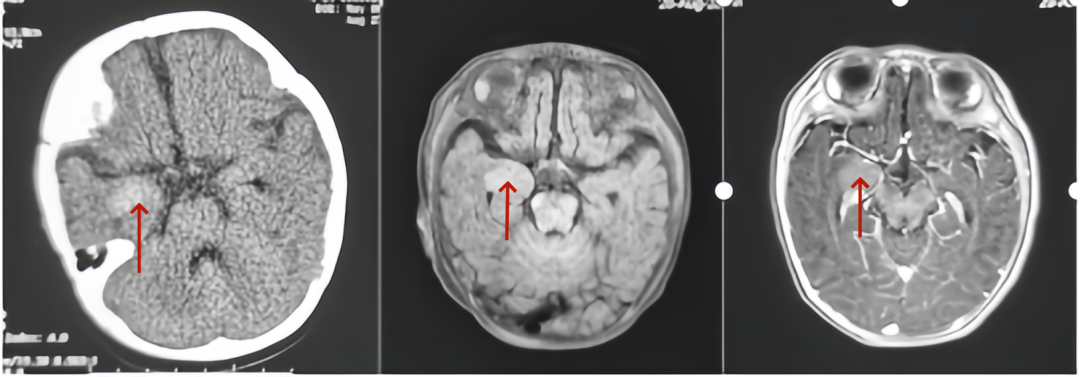

患儿术前CT及核磁影像,均可见右颞内侧占位